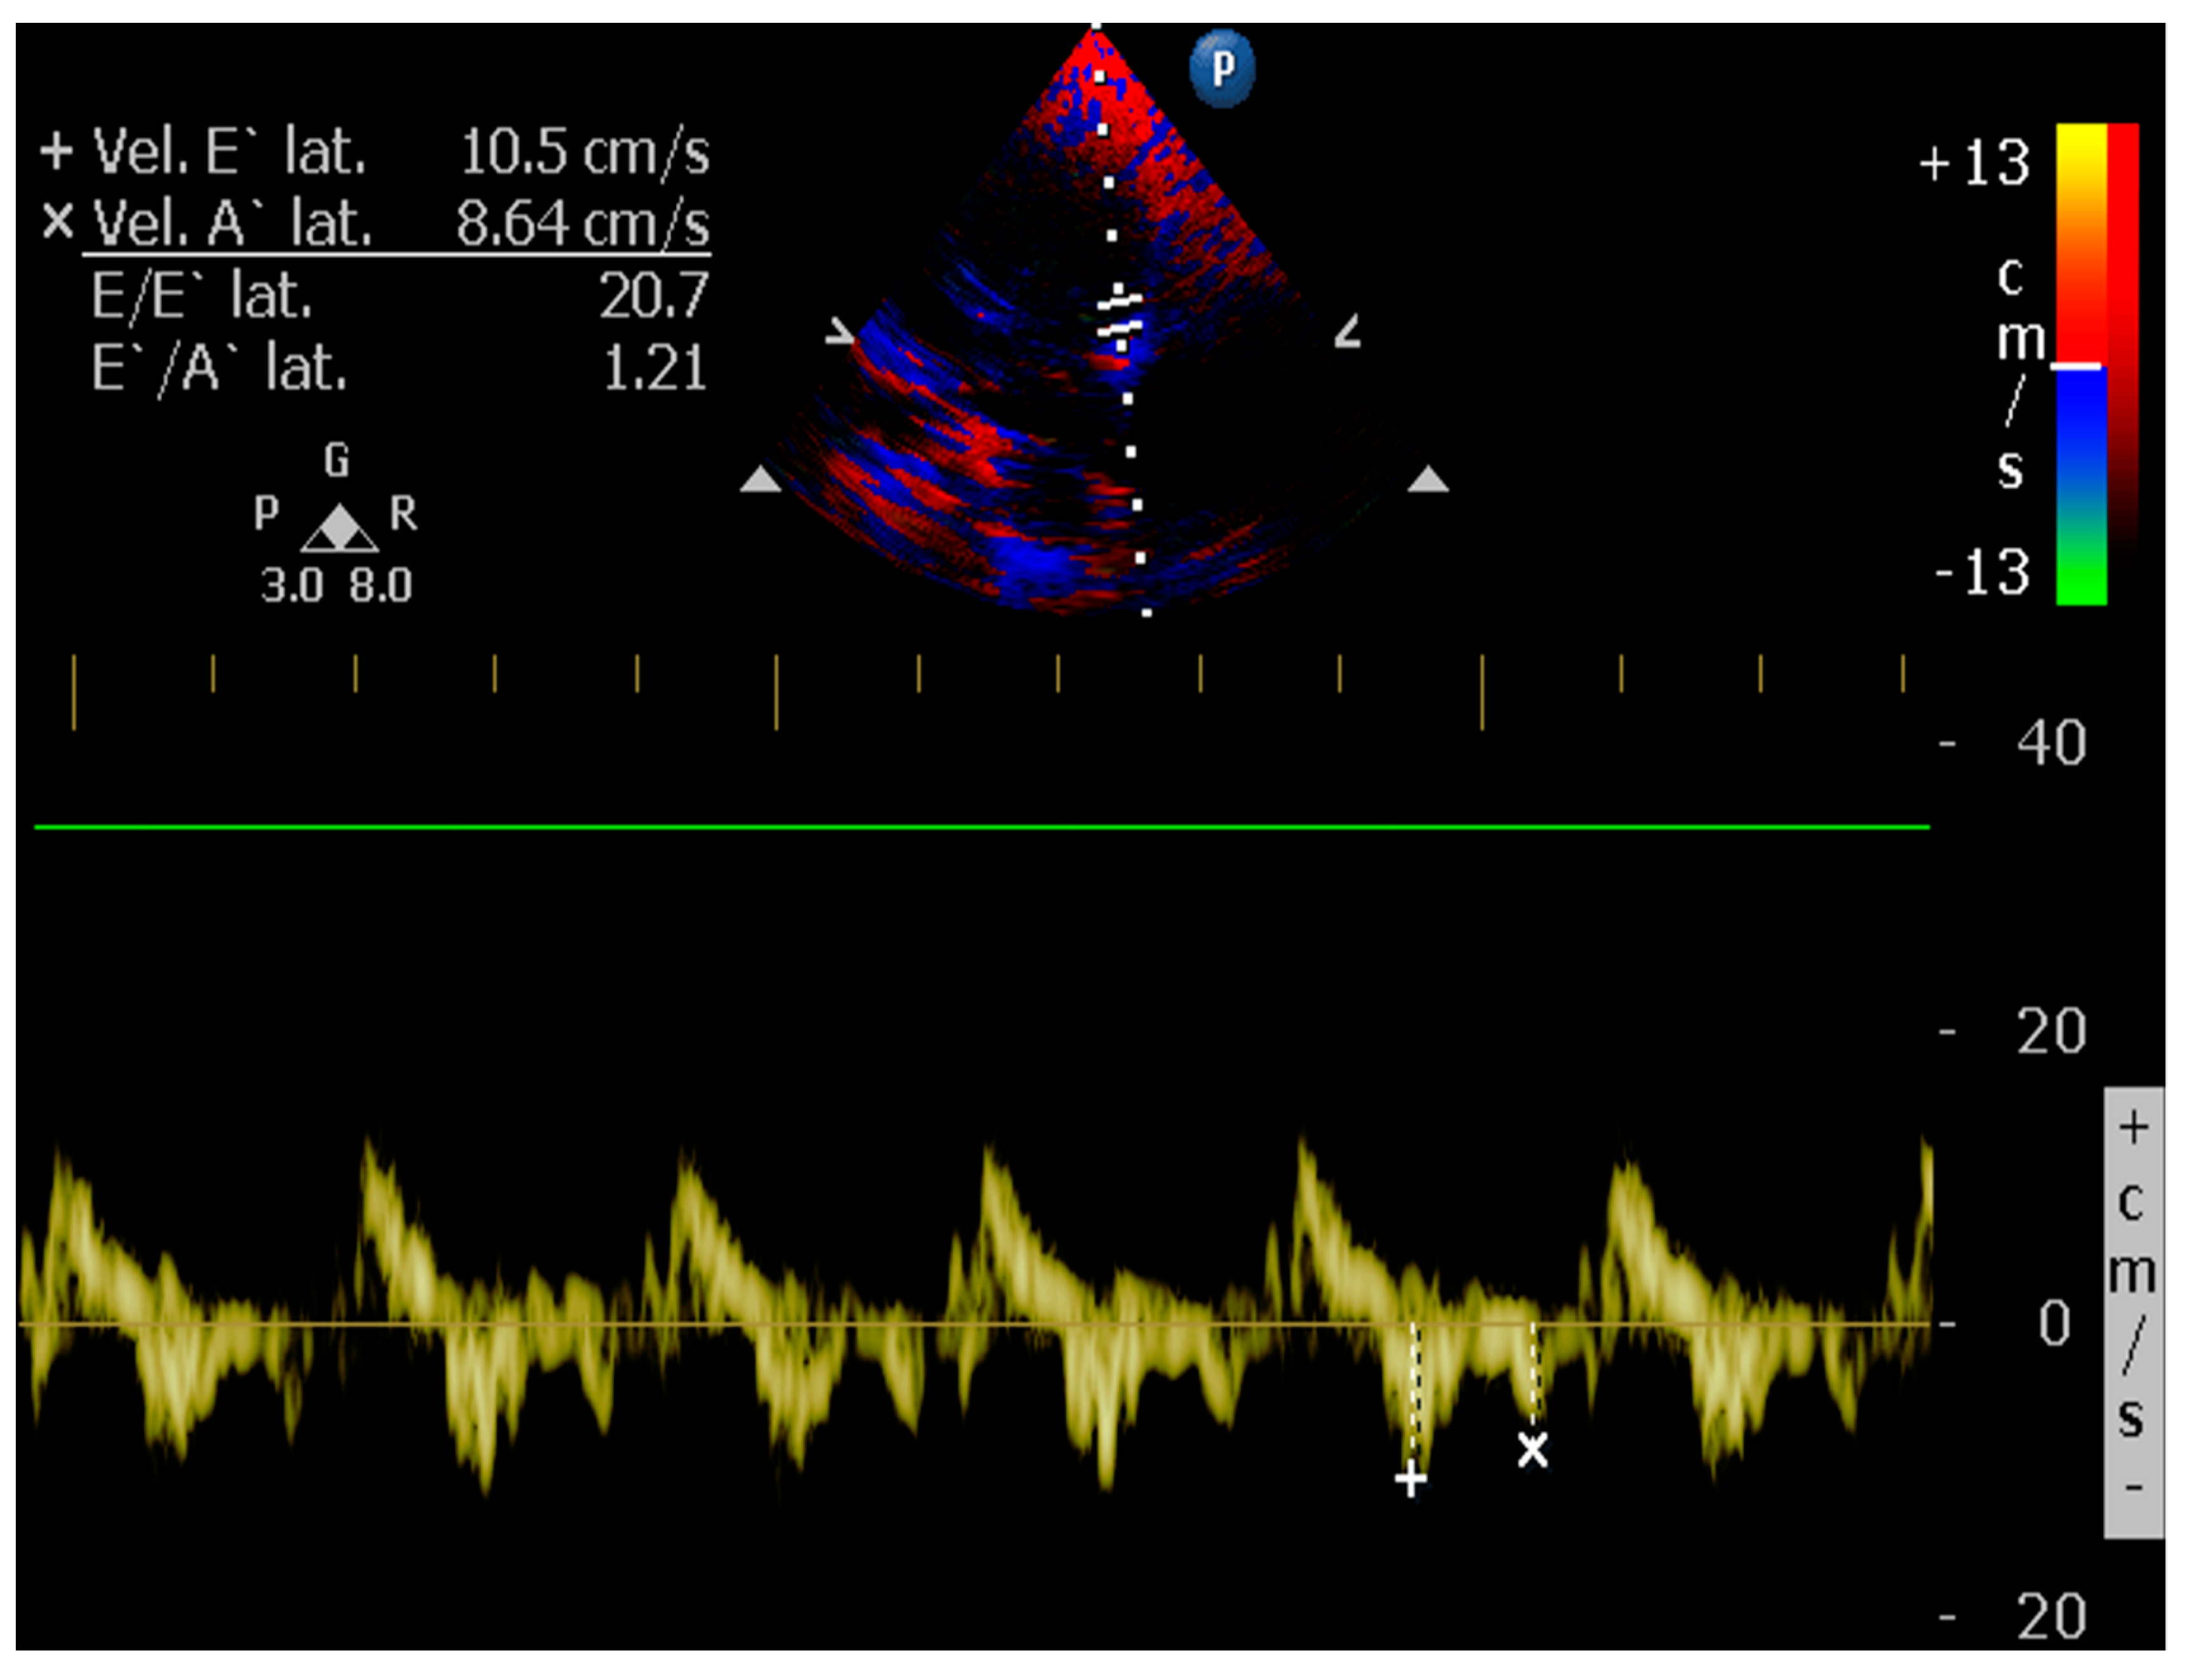

4.8.8. E/é Ratio of the Mitral Annulus

- Kim, J.H.; Park, H.M. Usefulness of conventional and tissue Doppler echocardiography to predict congestive heart failure in dogs with myxomatous mitral valve disease. J. Vet. Intern. Med. 2015, 29, 132–140. [Google Scholar] [CrossRef] [PubMed]

- Santos, M.; Rivero, J.; McCullough, S.D.; West, E.; Opotowsky, A.R.; Waxman, A.B.; Systrom, D.M.; Shah, A.M. E/e’ Ratio in Patients with Unexplained Dyspnea: Lack of Accuracy in Estimating Left Ventricular Filling Pressure. Circ. Heart Fail. 2015, 8, 749–756. [Google Scholar] [CrossRef]